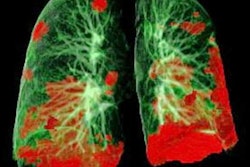

But the breast cancer wasn't the patient's only notable MRI finding. The reading radiologist also spotted incidental findings in the pulmonary space on the patient's MRI, including abnormal subpleural high T2 signal intensity in the lung periphery and enhancement in subpleural regions on postcontrast, fat-saturated T1-weighted images.

One day later, the patient experienced increased breathlessness and returned to the emergency department. A CT scan revealed bilateral subpleural ground-glass opacities with consolidation and multiple right lower lobe segmental acute pulmonary emboli, helping to strengthen the likelihood of COVID-19 infection.

While COVID-19 findings are well-documented for CT and chest radiography, the disease's presentation is not as well understood on MRI. Other reports have said COVID-19 can present similarly to other forms of pneumonia, including nonspecific high T2 signal intensity with enhancement on postcontrast T1 imaging.